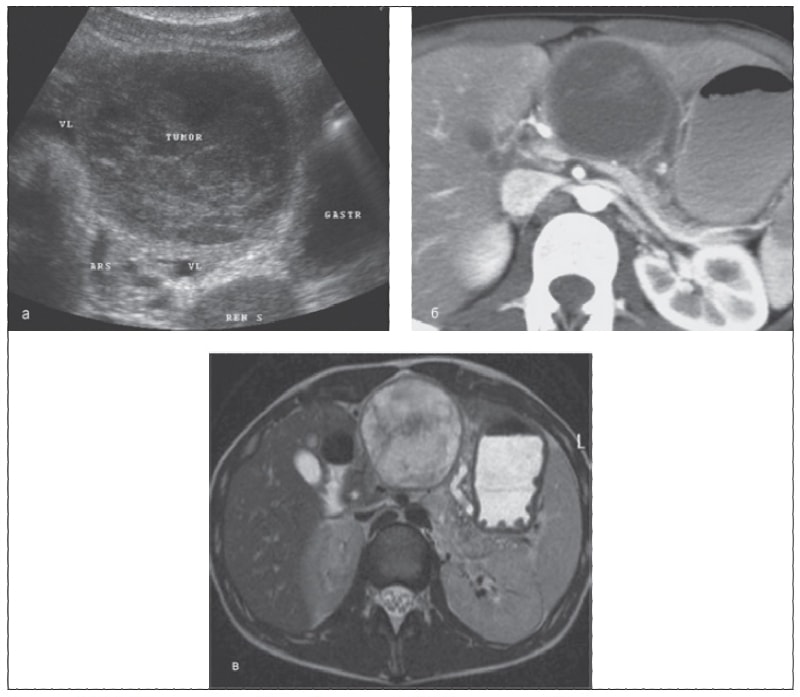

Компьютерная томография (КТ) – один из основных методов диагностики заболеваний легких. Однако анализ КТ-снимков требует высокой квалификации и опыта. Врачи должны внимательно изучать каждый снимок, чтобы выявить даже самые незначительные изменения. ИИ может значительно облегчить эту задачу. Нейронные сети, обученные на огромном количестве КТ-снимков, способны выявлять признаки заболеваний легких с высокой точностью. Мы, например, использовали ИИ для выявления очагов пневмонии, признаков рака легких и других патологий.

- Выявление пневмонии. ИИ может помочь выявить очаги пневмонии на ранних стадиях, что позволяет начать лечение вовремя и избежать осложнений.

- Диагностика рака легких. ИИ может помочь выявить признаки рака легких на ранних стадиях, когда лечение наиболее эффективно.

- Оценка степени повреждения легких при COVID-19. ИИ может помочь оценить степень повреждения легких при COVID-19 и спрогнозировать исход заболевания.

- Выявление туберкулеза. ИИ может помочь выявить признаки туберкулеза на КТ-снимках.